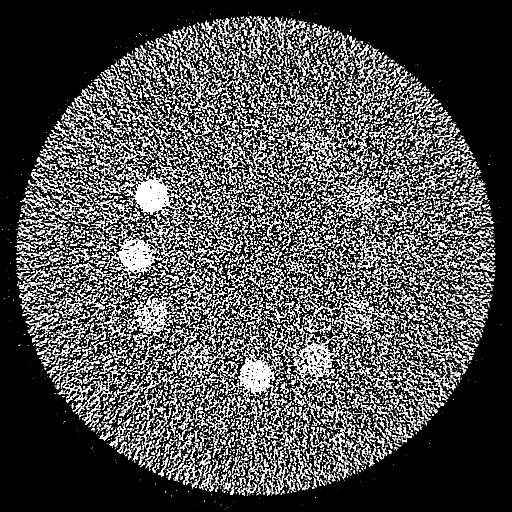

Reconstructed 35 – 85 keV Mono-Energetic Images

Conventional Physics-based Mono-Energetic Images

(30-cm cylindrical phantom)

Deep Learning-based Mono-Energetic Images